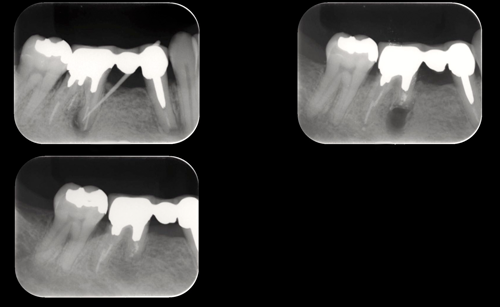

レントゲン撮影・CT撮影・口腔内Scan ・シュミレーションソフトによるプランニング

インプラント予定部位の骨の状態、周囲組織の状態を診査します。CTを用いることで多角的に診断することができます。当院では最新の歯科用コーンビームCTを設置し、低被爆を実現しています。